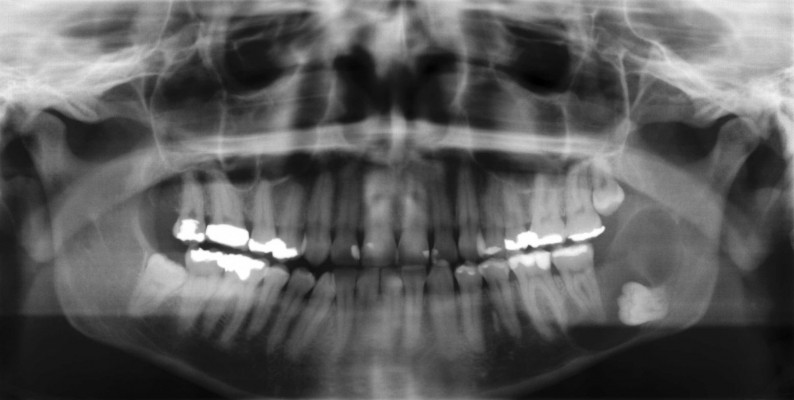

verlagerter Weisheitszahn

Weisheitszahn mit großer Zyste

extrem verlagerter Weisheitszahn mit großer Zyste

Verlauf der Unterkiefernerven

weit verlagerter Weisheitszahn